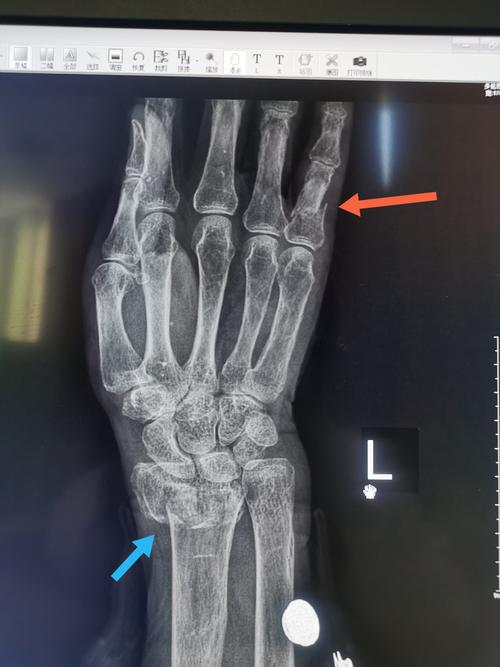

一例桡骨骨折,可以看到合并近端指骨骨折

桡骨小头骨折图片

桡骨小头骨折